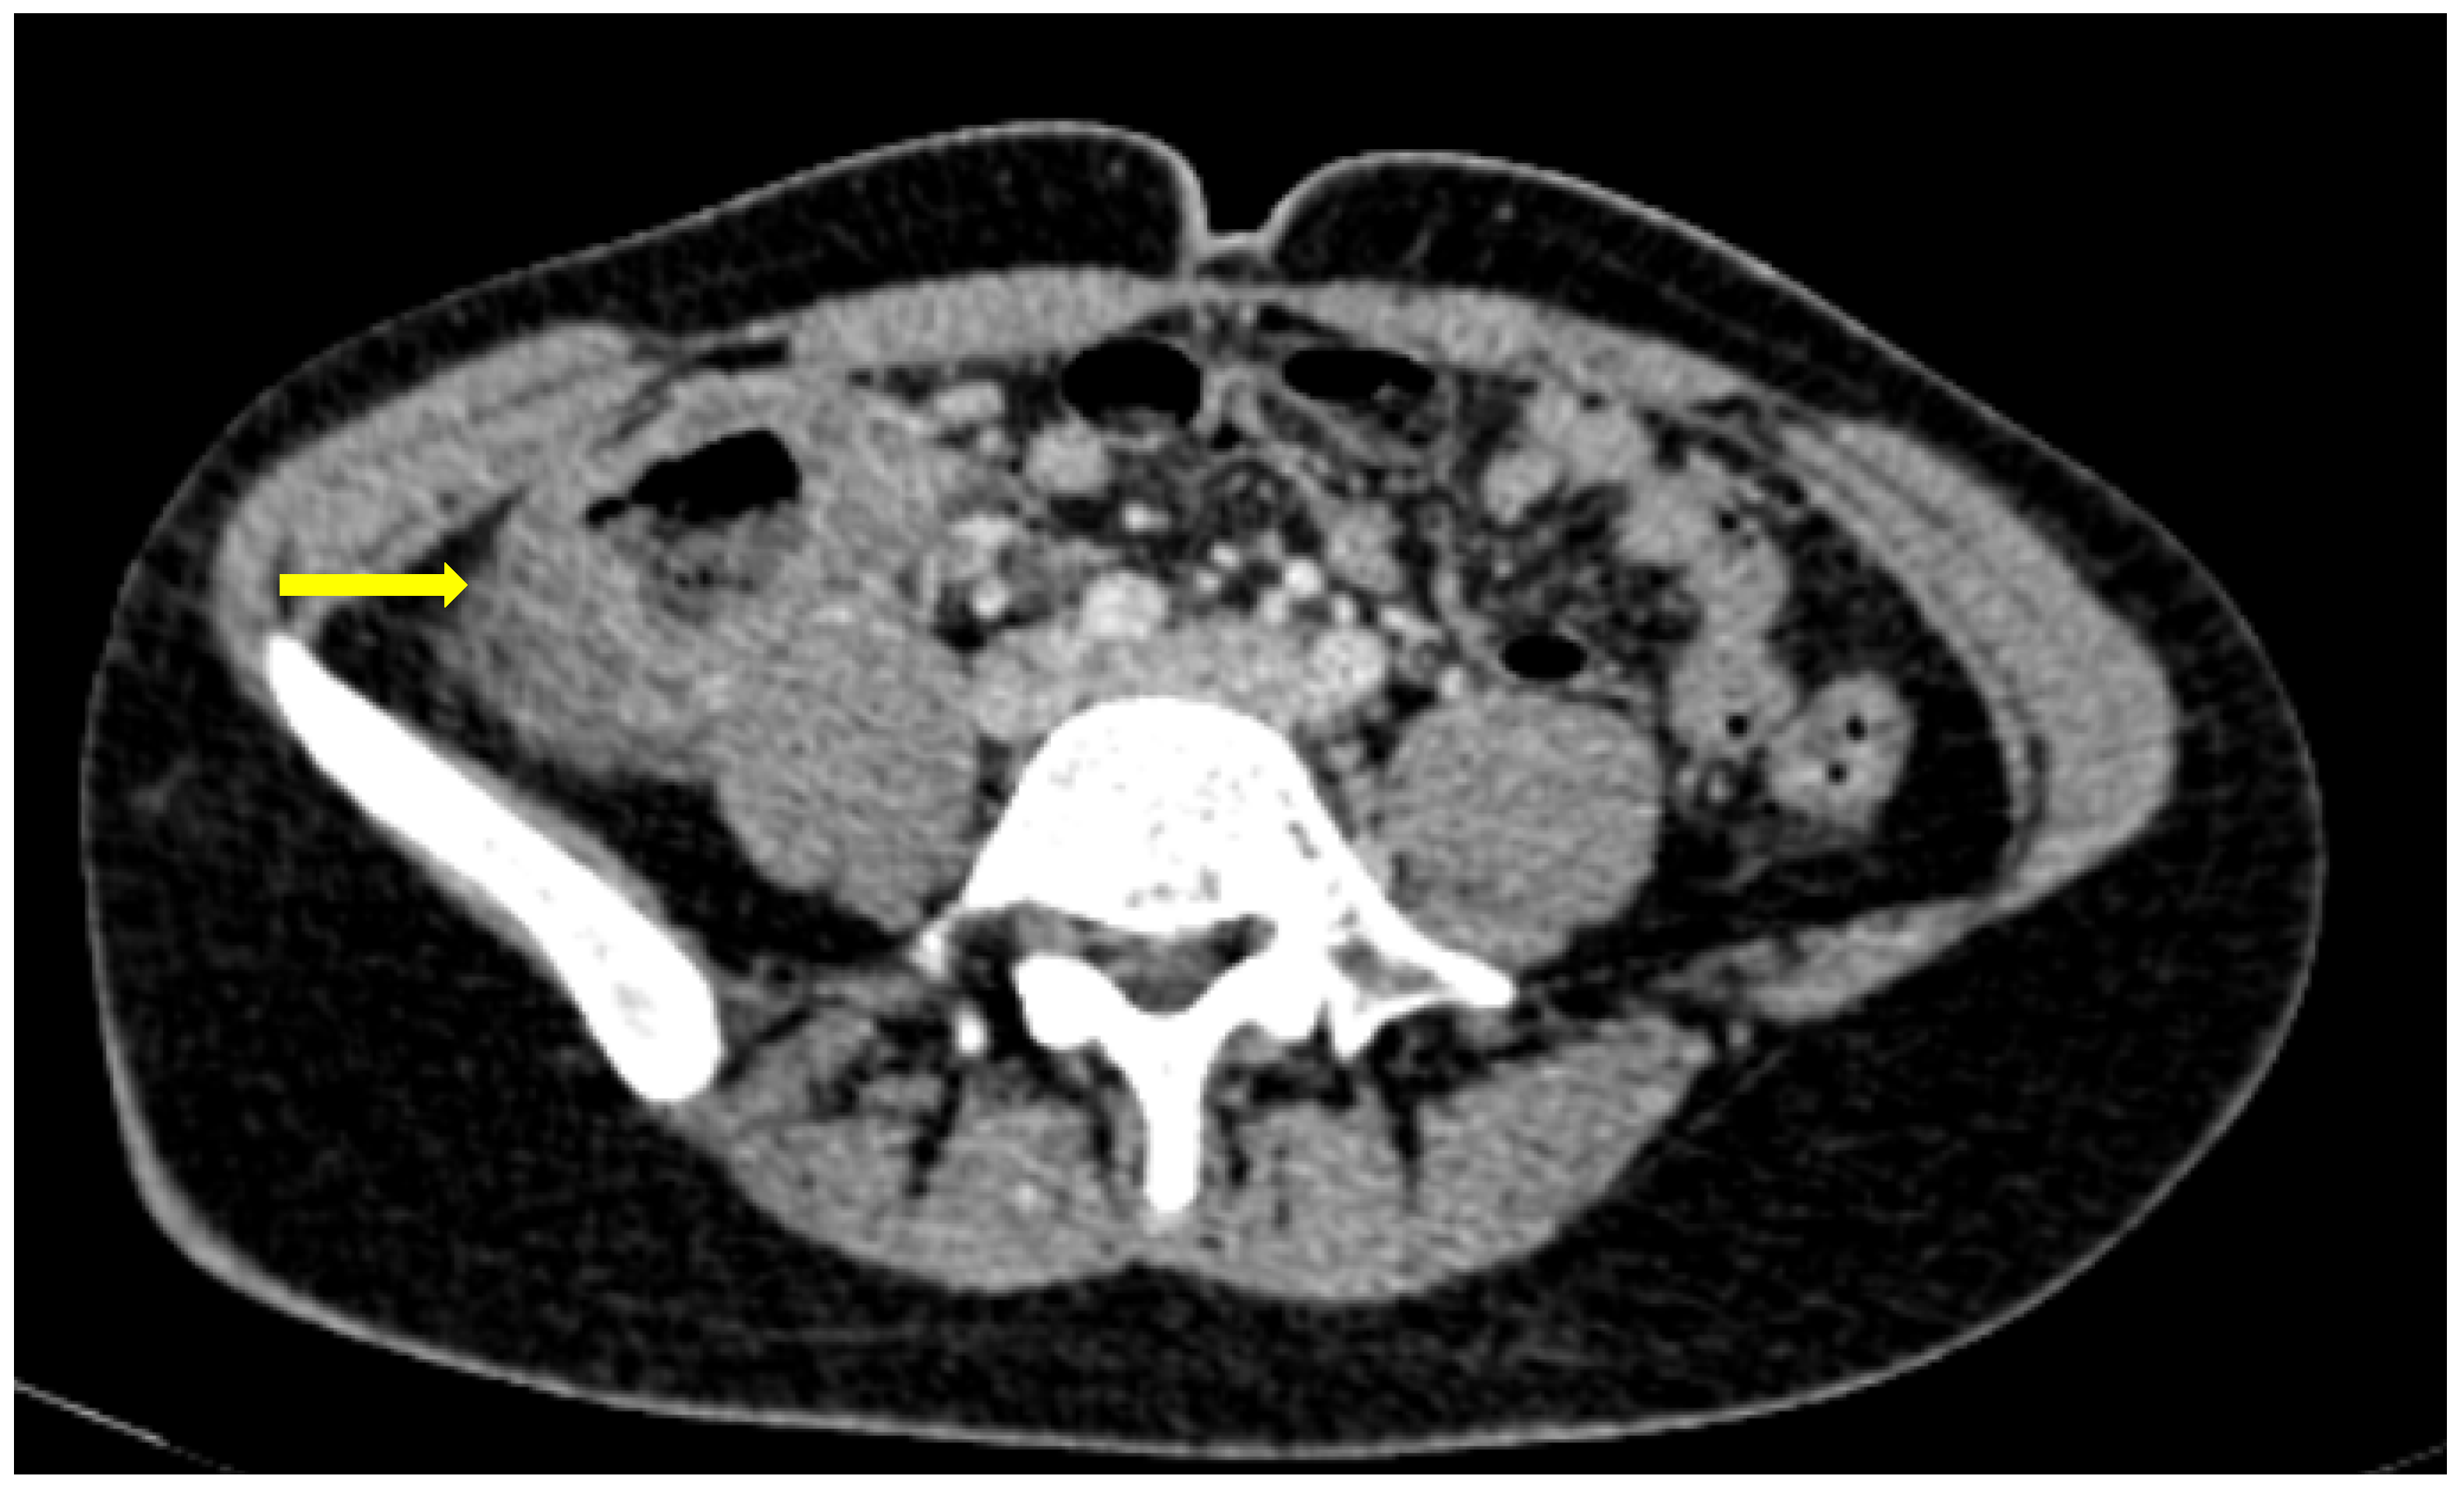

Figure 10. 56-year-old hospitalized male patient with COVID-19 pneumonia with raised level of d-dimers. CT depicting the thrombosed portal vein (yellow arrow). Note that in the same scan, there is extended small bowel thickening with mesenteric free fluid.

A single-center small retrospective study reported in COVID-19 patients 15 cases of acute aortic thrombosis, splenic artery thrombosis (associated with splenic infraction), superior mesenteric and renal artery thrombosis such as a celiac and an internal iliac thrombosis. An interesting part was a patient with infrarenal aortic wall inflammation and focal dissection, while many venous thromboses have been described (affecting the portal vein, inferior, superior mesenteric, renal, ovarian vein and inferior vena cava). Reports of indirect findings of the splanchnic branch venous occlusion described bowel wall severe edema, hyperenhancement or severe hypoenhancement, associated mesenteric and portal intravenous gas, bowel pneumatosis and pneumoperitoneum (Figure 10) [47]. Bari Dane et al. published a case of a simultaneous nonocclusive aortic, celiac and superior mesenteric artery thrombus combined with a complete common hepatic artery thrombus [48].

Those findings are in accordance with reports of bowel pneumatosis as a thrombotic event outcome [49], while many case reports and large case series demonstrate major abdominal—both arterial and venous—thrombosis in COVID-19 patients. In fact, many patients suffer from thrombotic occlusion despite prophylaxis or even the full-dose anticoagulation therapy supporting evidence of COVID-19 direct endothelial injury [50].